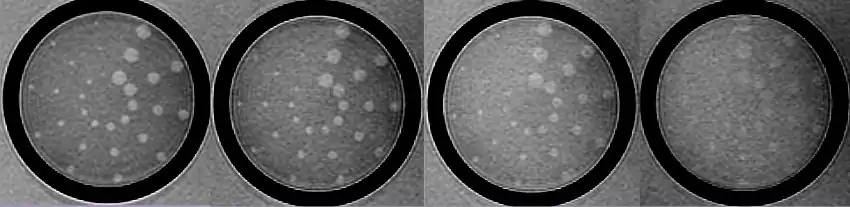

Contrast resolution is usually measured by generating a pattern from a test object that depicts how image contrast changes as the structures being imaged get smaller and closer together. The picture below shows one such set of images produced using the low contrast detectability inserts of the phantom employed in the MRI accreditation program of the American College of Radiology.